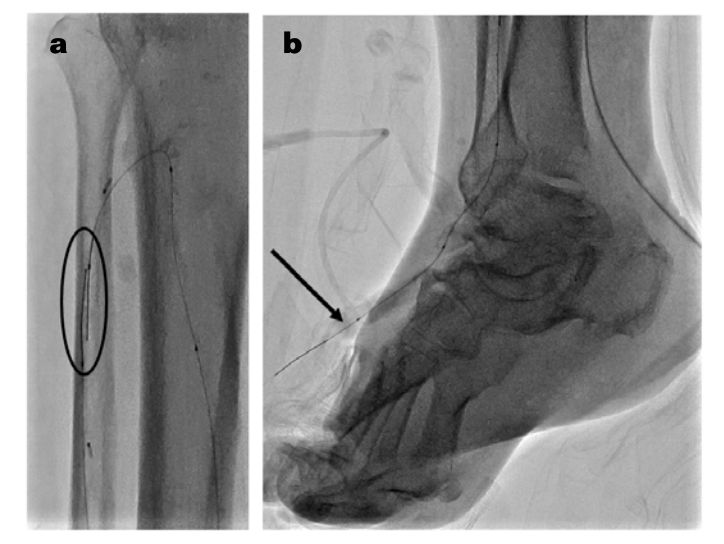

A 3.0 x 80 mm Advance Micro 14 2.5 Fr balloon (Cook Medical) was inserted through the retrograde AT 2.9 Fr sheath over the ViperWire, which was exchanged for an .014-inch Fielder XT (Asahi Intecc) and advanced distally to the 4 to 5 Fr Glidesheath Slender sheath PT access for intraarterial balloon tamponade to obtain hemostasis (Figure 7). Finally, the retrograde 2.9 Fr AT sheath was removed, and hemostasis was achieved with manual pressure (Figure 8). The patient tolerated the procedure well and ambulated an hour later. He underwent additional debridement and placement of a wound vac.

The TAMI approach has been well documented and can be utilized as an alternative in patients with high risk of complications related to transfemoral access. In other cases, we have used up to 5 to 6 and 6 to 7 Glidesheath Slender sheaths. To reduce the risk of access-related complications, we usually perform balloon tamponade with a 2.5 or 3.0 mm Advance Micro 14 2.5 Fr balloon through a distal 2.9 Fr sheath that can safely be closed with minimal manual pressure (Figure 9). We always utilize a hockey stick ultrasound probe to obtain access. We maintain an activated clotting time (ACT) >250 seconds during the case. We inject between 200 and 400 mcg of intra-arterial nitroglycerin for vasodilation and repeat the same process every thirty minutes.